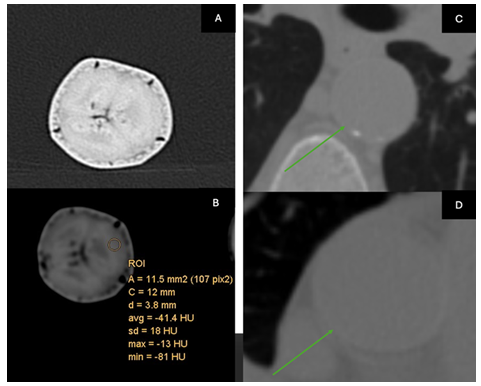

We evaluated density differences different models using Computed Tomography (CT) scanning. We compared a standard silicon suture pad (type and origin) against the tangerine / orange and the banana, our typically used home models, against structures like the aorta and skin. To ensure accuracy and comparability of our CT scan results, a calibration test of the CT scanner, using a standardized Hounsfield units (HU) phantom, was used. This step was crucial to account for potential variances between different CT scanners and to establish a baseline for HU measurements across all models.

The banana compares will with aortic tissue (Figure 1)

The suture pad’s density was recorded at approximately 265HU (Figure 3), the banana skin a was recorded at a maximum value of approximately 77HU, and the orange skin at a maximum value of approximately 304HU.

One of the pivotal, but not surprising, findings from our CT scan comparison is the variation in tissue density across different organic models. We are drawn to those exhibiting lower density levels, such as the banana. This characteristic renders the tissue less forgiving, necessitating delicate and more deliberate handling by the trainee. Such a trait is invaluable in surgical training as it mirrors the intricacies involved in managing human tissue during critical procedures [5]. A prime example highlighted in our study is the application of these handling principles to the aorta, especially in aortic dissection. The tissues are very friable and not forgiving of poor needle rotation. Likewise, in corneal transplant, irregular, poorly spaced interrupted sutures will result in blurred vision [17]. Precision and care are imperative. Low-fidelity models offer the nuanced understanding and application of these principles that significantly elevate a trainee's skill set and prepare them for the complexities of real-world surgical scenarios [18].